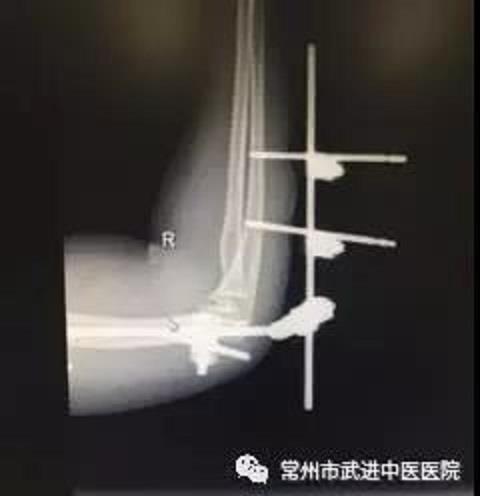

今年1月,王女士骑电动车不慎摔倒,导致右侧肘关节损伤,医院诊断为:肘关节脱位,冠状突骨折,桡骨小头骨折。王女士在全麻下行肘关节稳定术,术后予消肿、止痛等对症治疗处理。3个月后拆除外固定。

术后DR片(上)

外固定拆除后DR片(下) 王女士住院后,康复医生做了详细的功能评定。